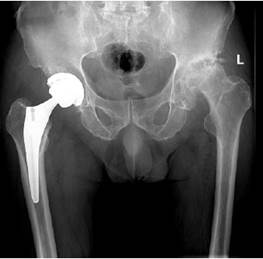

患者术前X线片

(本次计划左髋关节置换)▼